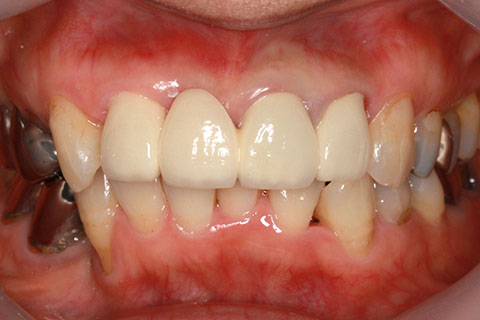

オールセラミックの症例3

古くなった被せをジルコニアセラミックスで治療。

- 年齢・性別

- 60歳女性

- 治療期間

- 1ヶ月

- 抜歯

- なし

- 治療費

- 35.2万円

- 備考

- 古くなった被せを新たなセラミックス冠にする。

- 治療内容

- 歯質を削除し、セラミック冠をセメント合着

- 施術の副作用(リスク)

- 知覚過敏、歯髄炎、荷重負担